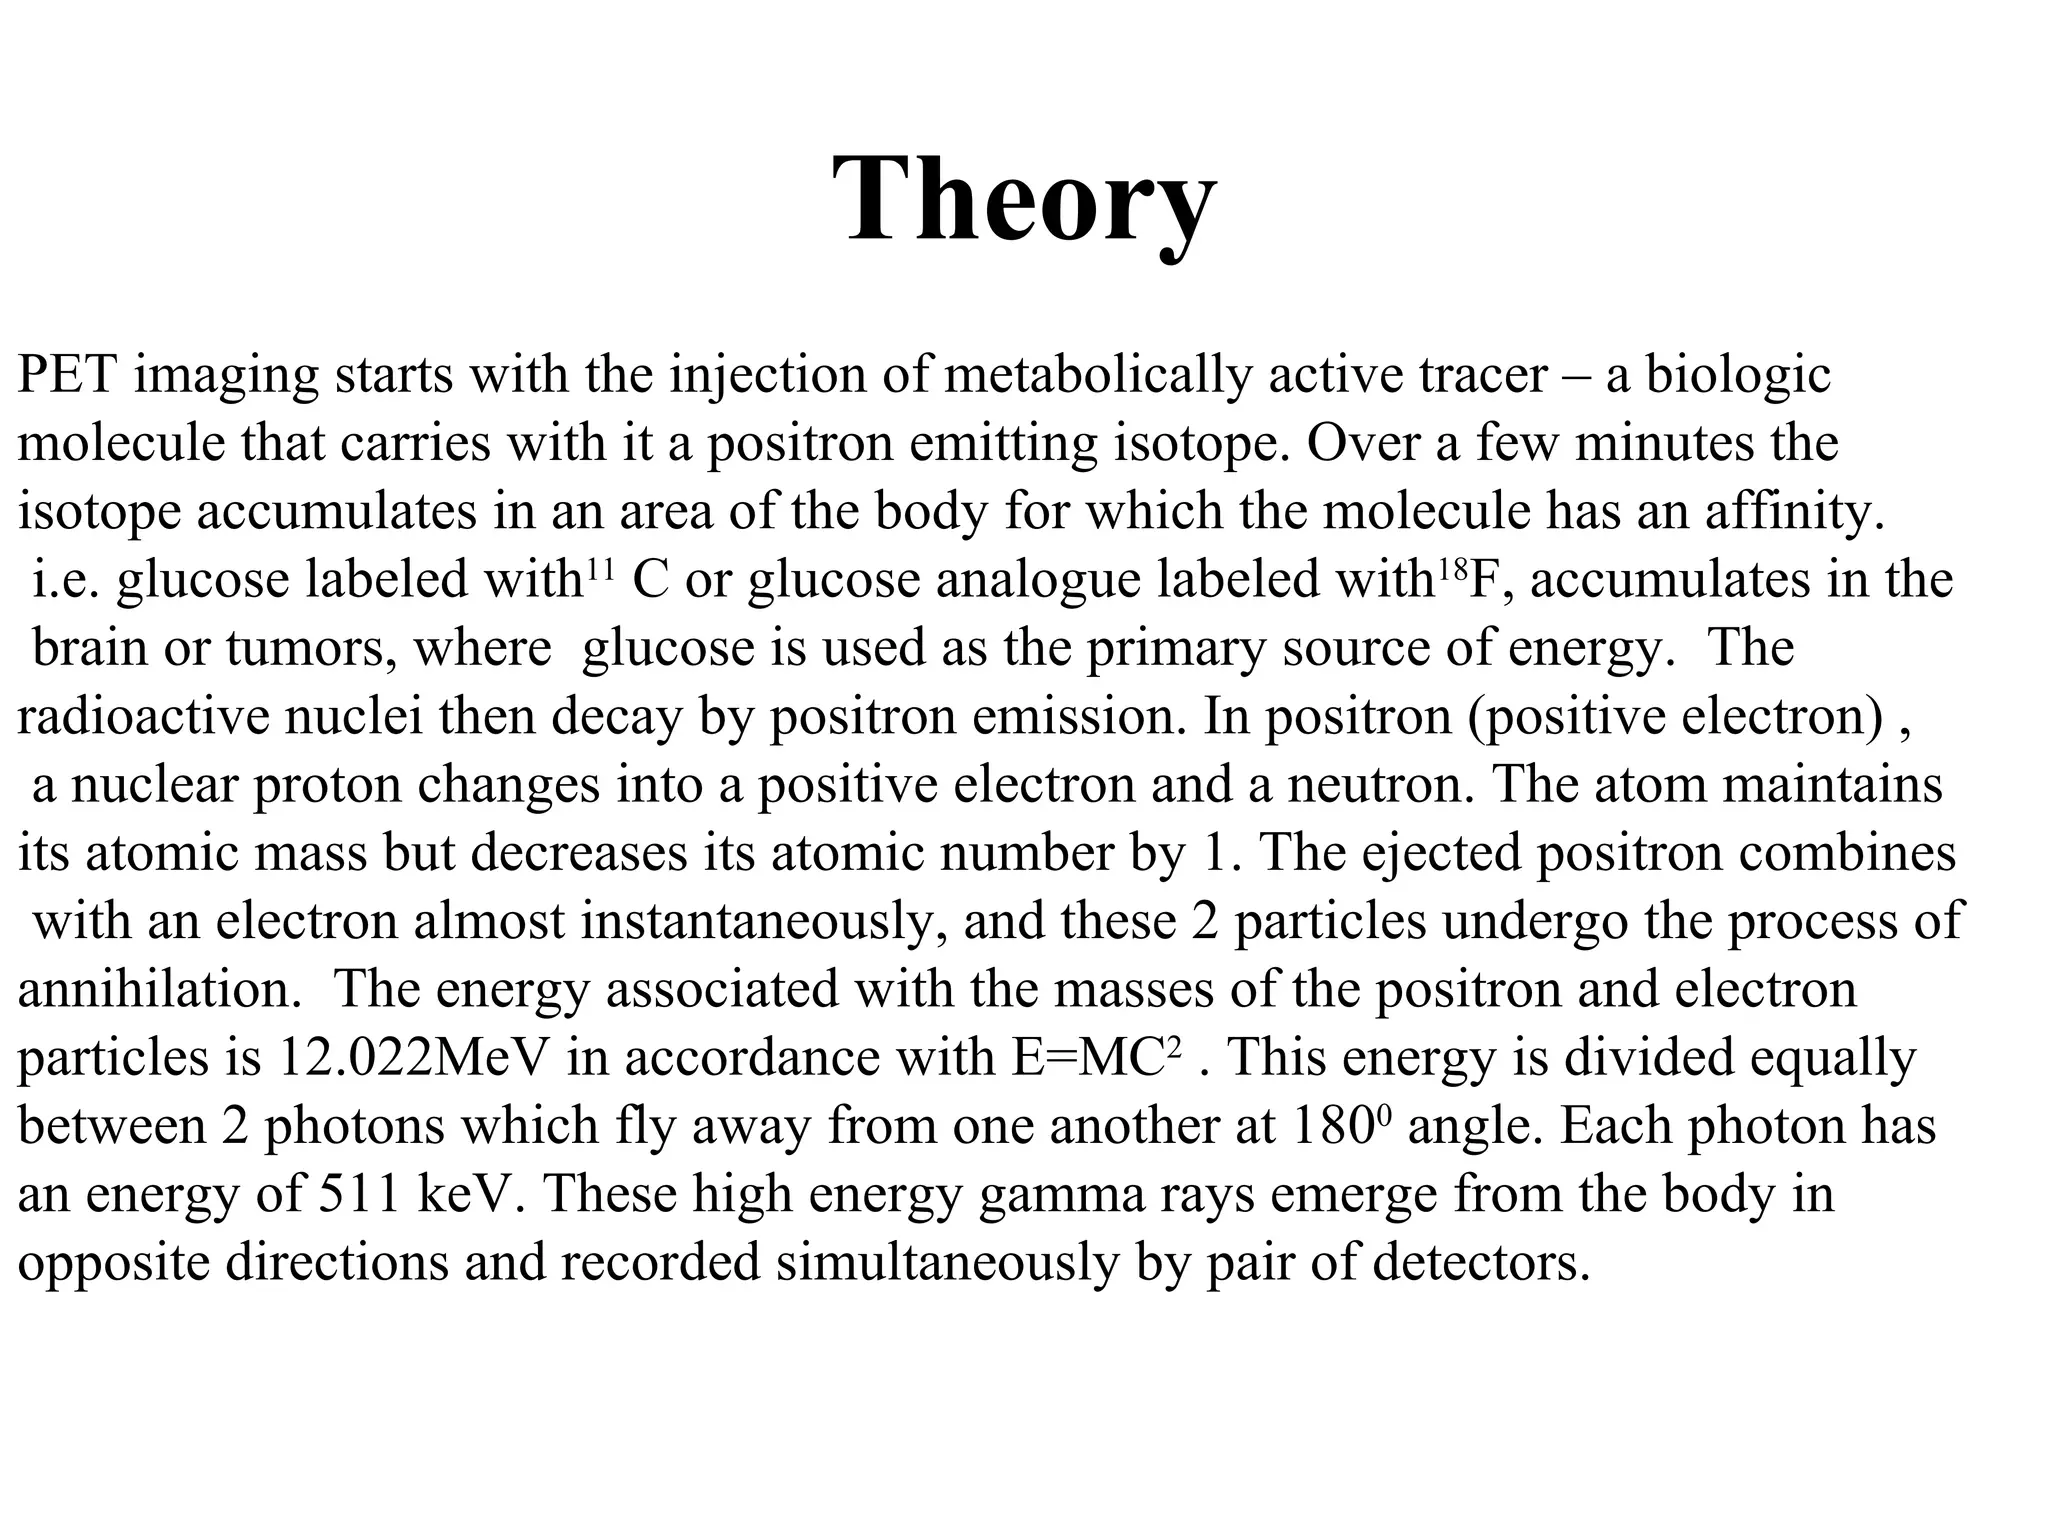

The document discusses various medical imaging modalities including x-rays, computed tomography (CT), and digital mammography. It describes the basic principles and historical development of these technologies, how images are formed, and what types of anatomical features and abnormalities they can detect. Key advances include the development of digital systems that allow image manipulation and remote consultation. While promising, digital mammography still faces challenges around resolution and cost.